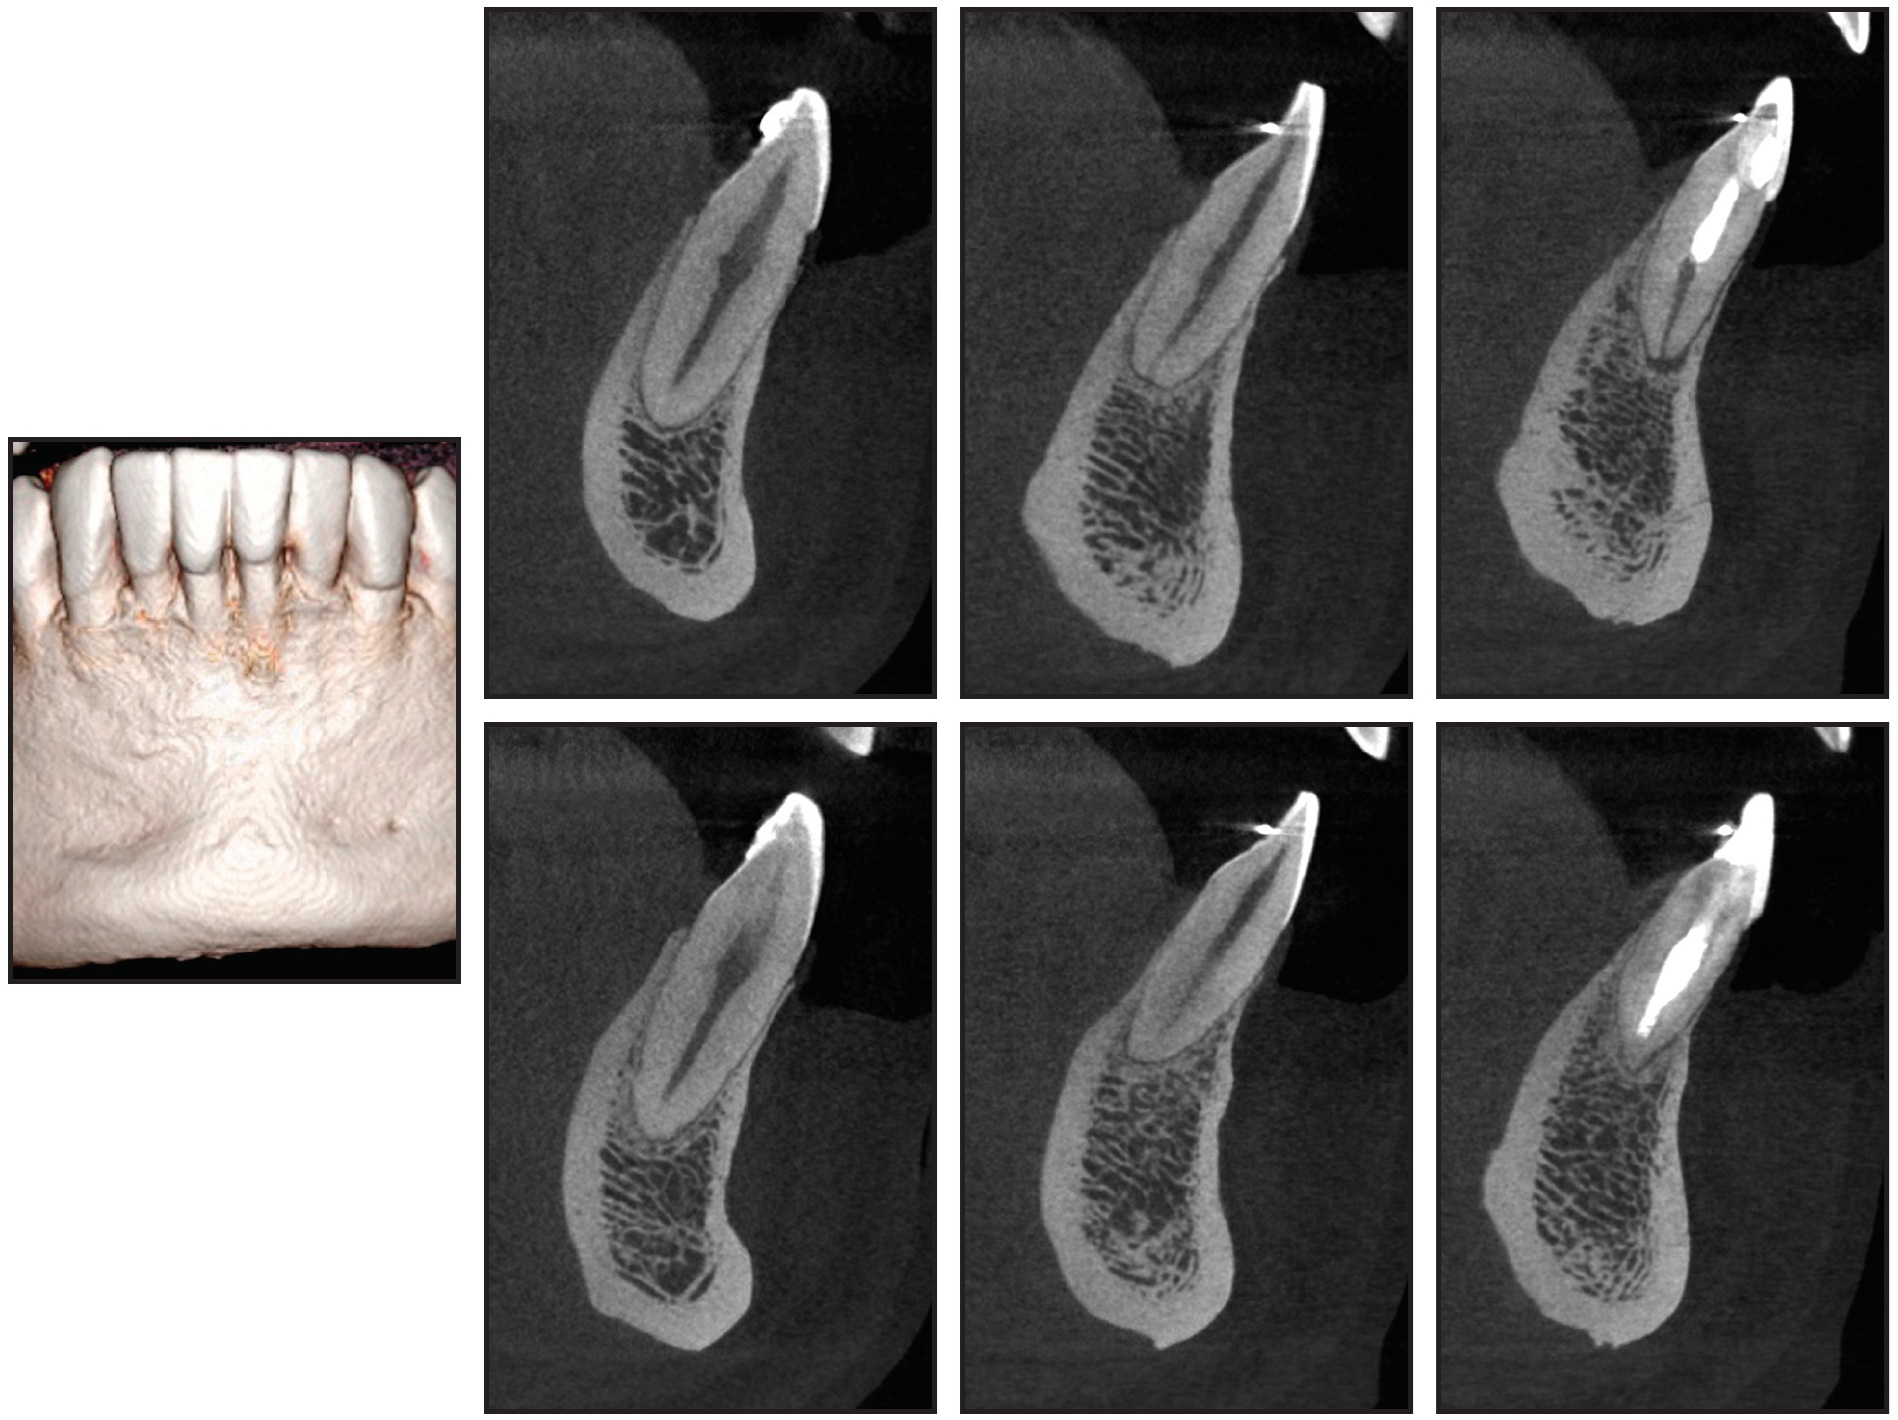

Post-treatment computed tomographic (CT) images confirmed that the integrity of the alveolar bone and the dental roots was maintained (Fig. 7).

Fig. 7 Preservation of alveolar bone tissue and dental roots after treatment.

The lower central incisors showed the greatest alveolar bone loss, but the damage was minimal. Unfortunately, a CT scan was not required before orthodontic treatment, and therefore it is not possible to determine whether this bone loss was preexistent or caused by orthodontic tooth movement. In any event, the overall results were excellent, and the cost-benefit return of the orthodontic treatment was unquestionable.